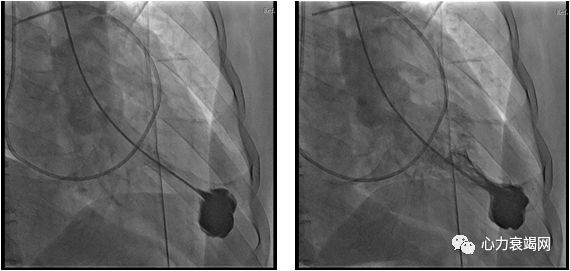

心尖部室壁瘤

左心室中部收缩期梗阻或闭塞呈“沙漏形”或“哑铃形

心尖2.0×2.5cm大小变薄,未见明显膨出及矛盾运动,1-0线带毛毡片两针褥式折叠

停机后窦性心律,血压110/50mmHg,左室心尖至流出道通畅,无压差,二尖瓣微量反流,三尖瓣及主动脉瓣无反流